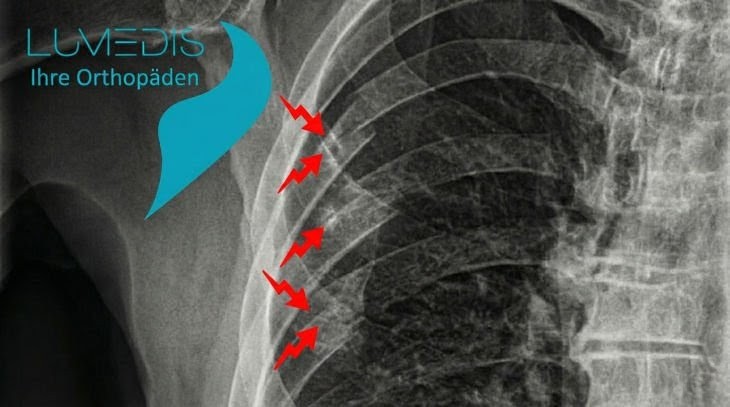

Röntgenbild einer Rippenserienfraktur rechts

Rippenserienfraktur rechts der 4., 5. und 6. Rippe